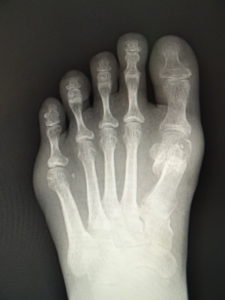

おおむね、外反角が30度以上になると、保存治療はもはやあまり有効ではありません。症状が強く、患者さんと良く吟味の上、希望されれば手術へと進みます。他に根治療法はないが、手術なら根治できます(図5)。ただMP関節の変性性変化があると、痛みや拘縮が残ることがあります。

(図5)

手術前 手術後4年

(図6)

手術前 手術後

(図7)

真田理事長による手術の様子。外反母趾|症例 (左から 手術前、手術後、ワイヤ抜去後)